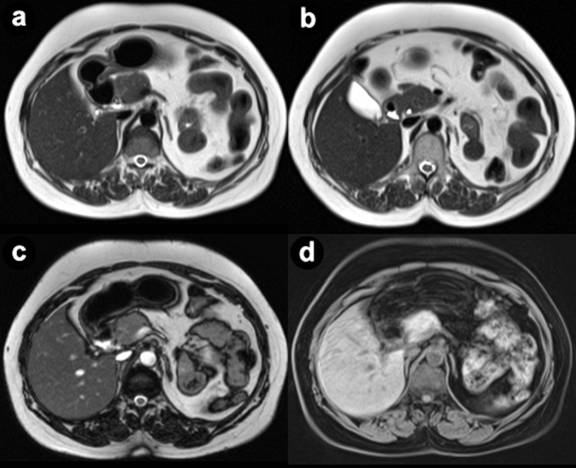

Pseudo-agenesis of the pancreas refers to the atrophy of the pancreatic body and tail secondary to acute/chronic pancreatitis with sparing of the head and uncinate process. MRCP/ERCP provide conclusive diagnosis in this condition by demonstrating minor ductal system in pseudoagenesis due to acquired pancreatic atrophy and its absence in dorsal pancreatic agenesis / pancreatic hypoplasia [2] (Figures 2, 3, and 4). Ultrasound is relatively insensitive in this regard and CT may not be sensitive always.

Figure 2. Axial T2 weighted MRI images (a., b.), TRUFI image (c.) and T1 fat sat image (d.) showing normal head and uncinate process of the pancreas with non-visualization of neck, body and tail. |